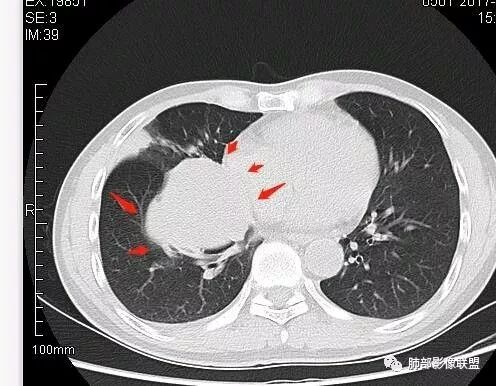

崇军:右侧中叶支气管与下叶支气管夹角处的肿块,支气管没有堵塞仅仅推移,不是支气管来源,纵隔来源也可以排除;跨叶,边界清,平扫无明显坏死,来源只剩下淋巴,血管与胸膜,如果是淋巴,纵隔未见其他淋巴结,淋巴瘤排除,巨淋巴增生症可能,血管来源,PSP可能,胸膜来源,SFT可能,这三者没有增强难鉴别。张帅:病灶边缘光滑,气管挤压呈贴边征,赞同王崇军老师观点:增大淋巴结,但同时需鉴别PSP及类癌。

南边:这类片其实很艰难Shelia:应该有个增强崇军:是的,如果没有老师您以前的讲述,一个肺门占位就发出去了风儿:肿块跨叶生长,边缘光滑,有膨隆有平直,支气管血管受压,病灶后方支气管似乎进入病灶后堵塞,与纵隔胸膜呈锐角,来源肺内-神经内分泌肿瘤?胸膜-SFT?血管-PSP?临近心包少量积液右侧胸腔少量积液是否与肿块有关

初学者:如果中叶病灶,叶间裂应该下推,也不会上推

而且支气管內密度较高是粘液栓,远端支气管也是通畅,所以支气管内是因为受压所以痰液引流不畅。

南边:从叶裂的变形,下朝上,越来越朝前扭曲,提示叶裂局部有朝前上推移的趋势

南边:病灶边界清,提示侵袭性弱,膨胀生长为主;这时候我们提示病灶不应该是支气管关系密切,提示间叶来源或胸膜来源

深分叶,警惕恶性

常规考虑:1、肉瘤首先考虑

2、胸膜孤立性纤维瘤待排